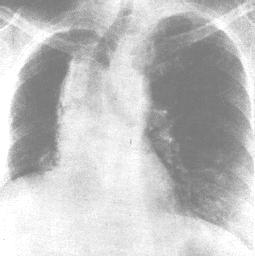

肺功能改變:肺放射性肺炎和纖維化都引起限制性通氣功能障礙,肺順應性減低,伴通氣/血流比例降低和彌散功能減低,導致缺氧。有時胸片尚未發現異常,而肺功能檢查已顯示變化。 X線表現:多數於停止放療一月後,肺部出陰影。急性期在照射的肺野上出現彌溫性片狀模糊陰影,其間隱約可見網狀影,酷似支氣管肺炎或肺水腫。病變的範圍與胸廓表面照射野一致。慢性發生肺纖維化,呈條索狀或團塊狀收縮或局限性肺不張。縱隔胸膜和心包有大量粘連,縱隔向患側移位,同側橫膈升高和胸廓塌陷。

放射性肺炎“放射性肺炎”的診斷一般並不複雜,可根據如下依據進行診斷:有放射性治療史;病人有乾性嗆咳、進行性氣急及肺部的Velcro羅音具有特徵性;胸部X線檢查可見肺部炎症或纖維化表現。多於停止放射治療一個月後出現。急性期表現為在照射肺野出現片狀或溶合成大片、緻密的模糊陰影,其間隱約可見網狀陰影,與支氣管肺炎或肺水腫極為相似。慢性期表現為肺纖維化,呈網狀,條索狀或團塊狀收縮陰影,主要分布於肺門或縱隔兩側及其他放射肺野。由於肺纖維收縮,氣管、心臟向患側移位,同側橫膈抬高,正常肺組織產生代償性肺氣腫。發生肺動脈高壓時,表現為肺動脈段突出或右心肥大。常有胸腔積液特徵。特別注意的是需與肺轉移性癌相鑑別,如果將放射性肺部損傷誤作為肺轉移性腫瘤,繼續放療,可造成死亡。放射性肺損傷的部位一般與照射野相符,經過一段時間觀察肺纖維化後病灶會回縮,而轉移癌會繼續增大。為了預防放射性肺損傷的發生,應嚴格掌握放射野、時間和劑量,以儘量避免肺部的損傷。